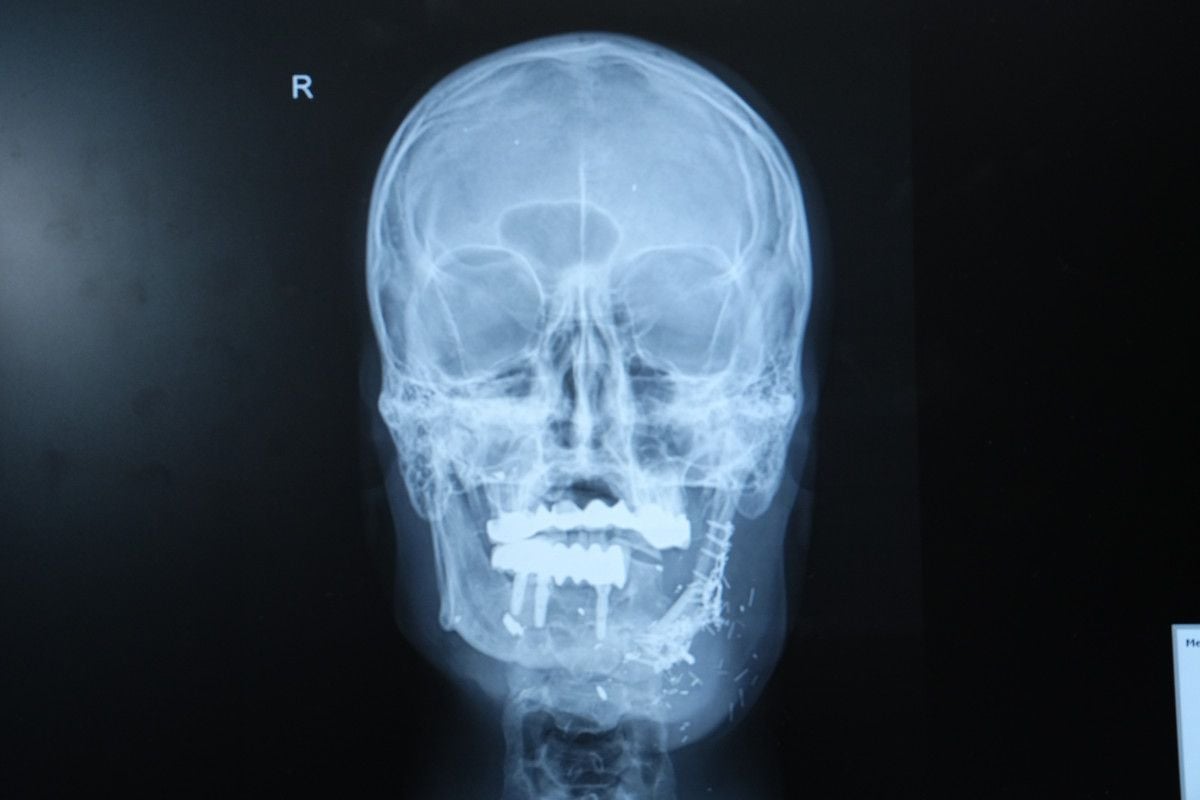

Doç. Dr. Burak Özkan, hastanın durumunun oldukça karmaşık olduğunu belirterek, “Hastamız ateşli silah yaralanması sonrası çenesinin yarısını kaybetmişti. Daha önce farklı merkezlerde ameliyat olmuş fakat nakiller başarısız olmuştu. Hem çene bütünlüğünü sağlamak hem de ileride implant yapılabilecek sağlam bir kemik dokusu oluşturmak gerekiyordu. Hastanın bacağından aldığımız kemiği mikrocerrahi yöntemle çeneye naklettik. Damarlara bağlantı yaptık, plaklarla sabitledik. Bu sayede hem fonksiyonel hem de estetik olarak başarılı bir sonuç elde ettik.”

Doç. Dr. Burak Özkan, mikrocerrahinin bu tür vakalarda büyük önem taşıdığını vurgulayarak, “Kompozit doku eksikliklerinde vaskülerkemik transferi bize büyük avantaj sağlıyor. Hastamız şu an kendi beslenmesini sağlayabiliyor. Önümüzdeki süreçte kemik iyileşmesini tamamladıktan sonra diş implantları yerleştireceğiz ve hastamız çok daha rahat beslenebilecek.”